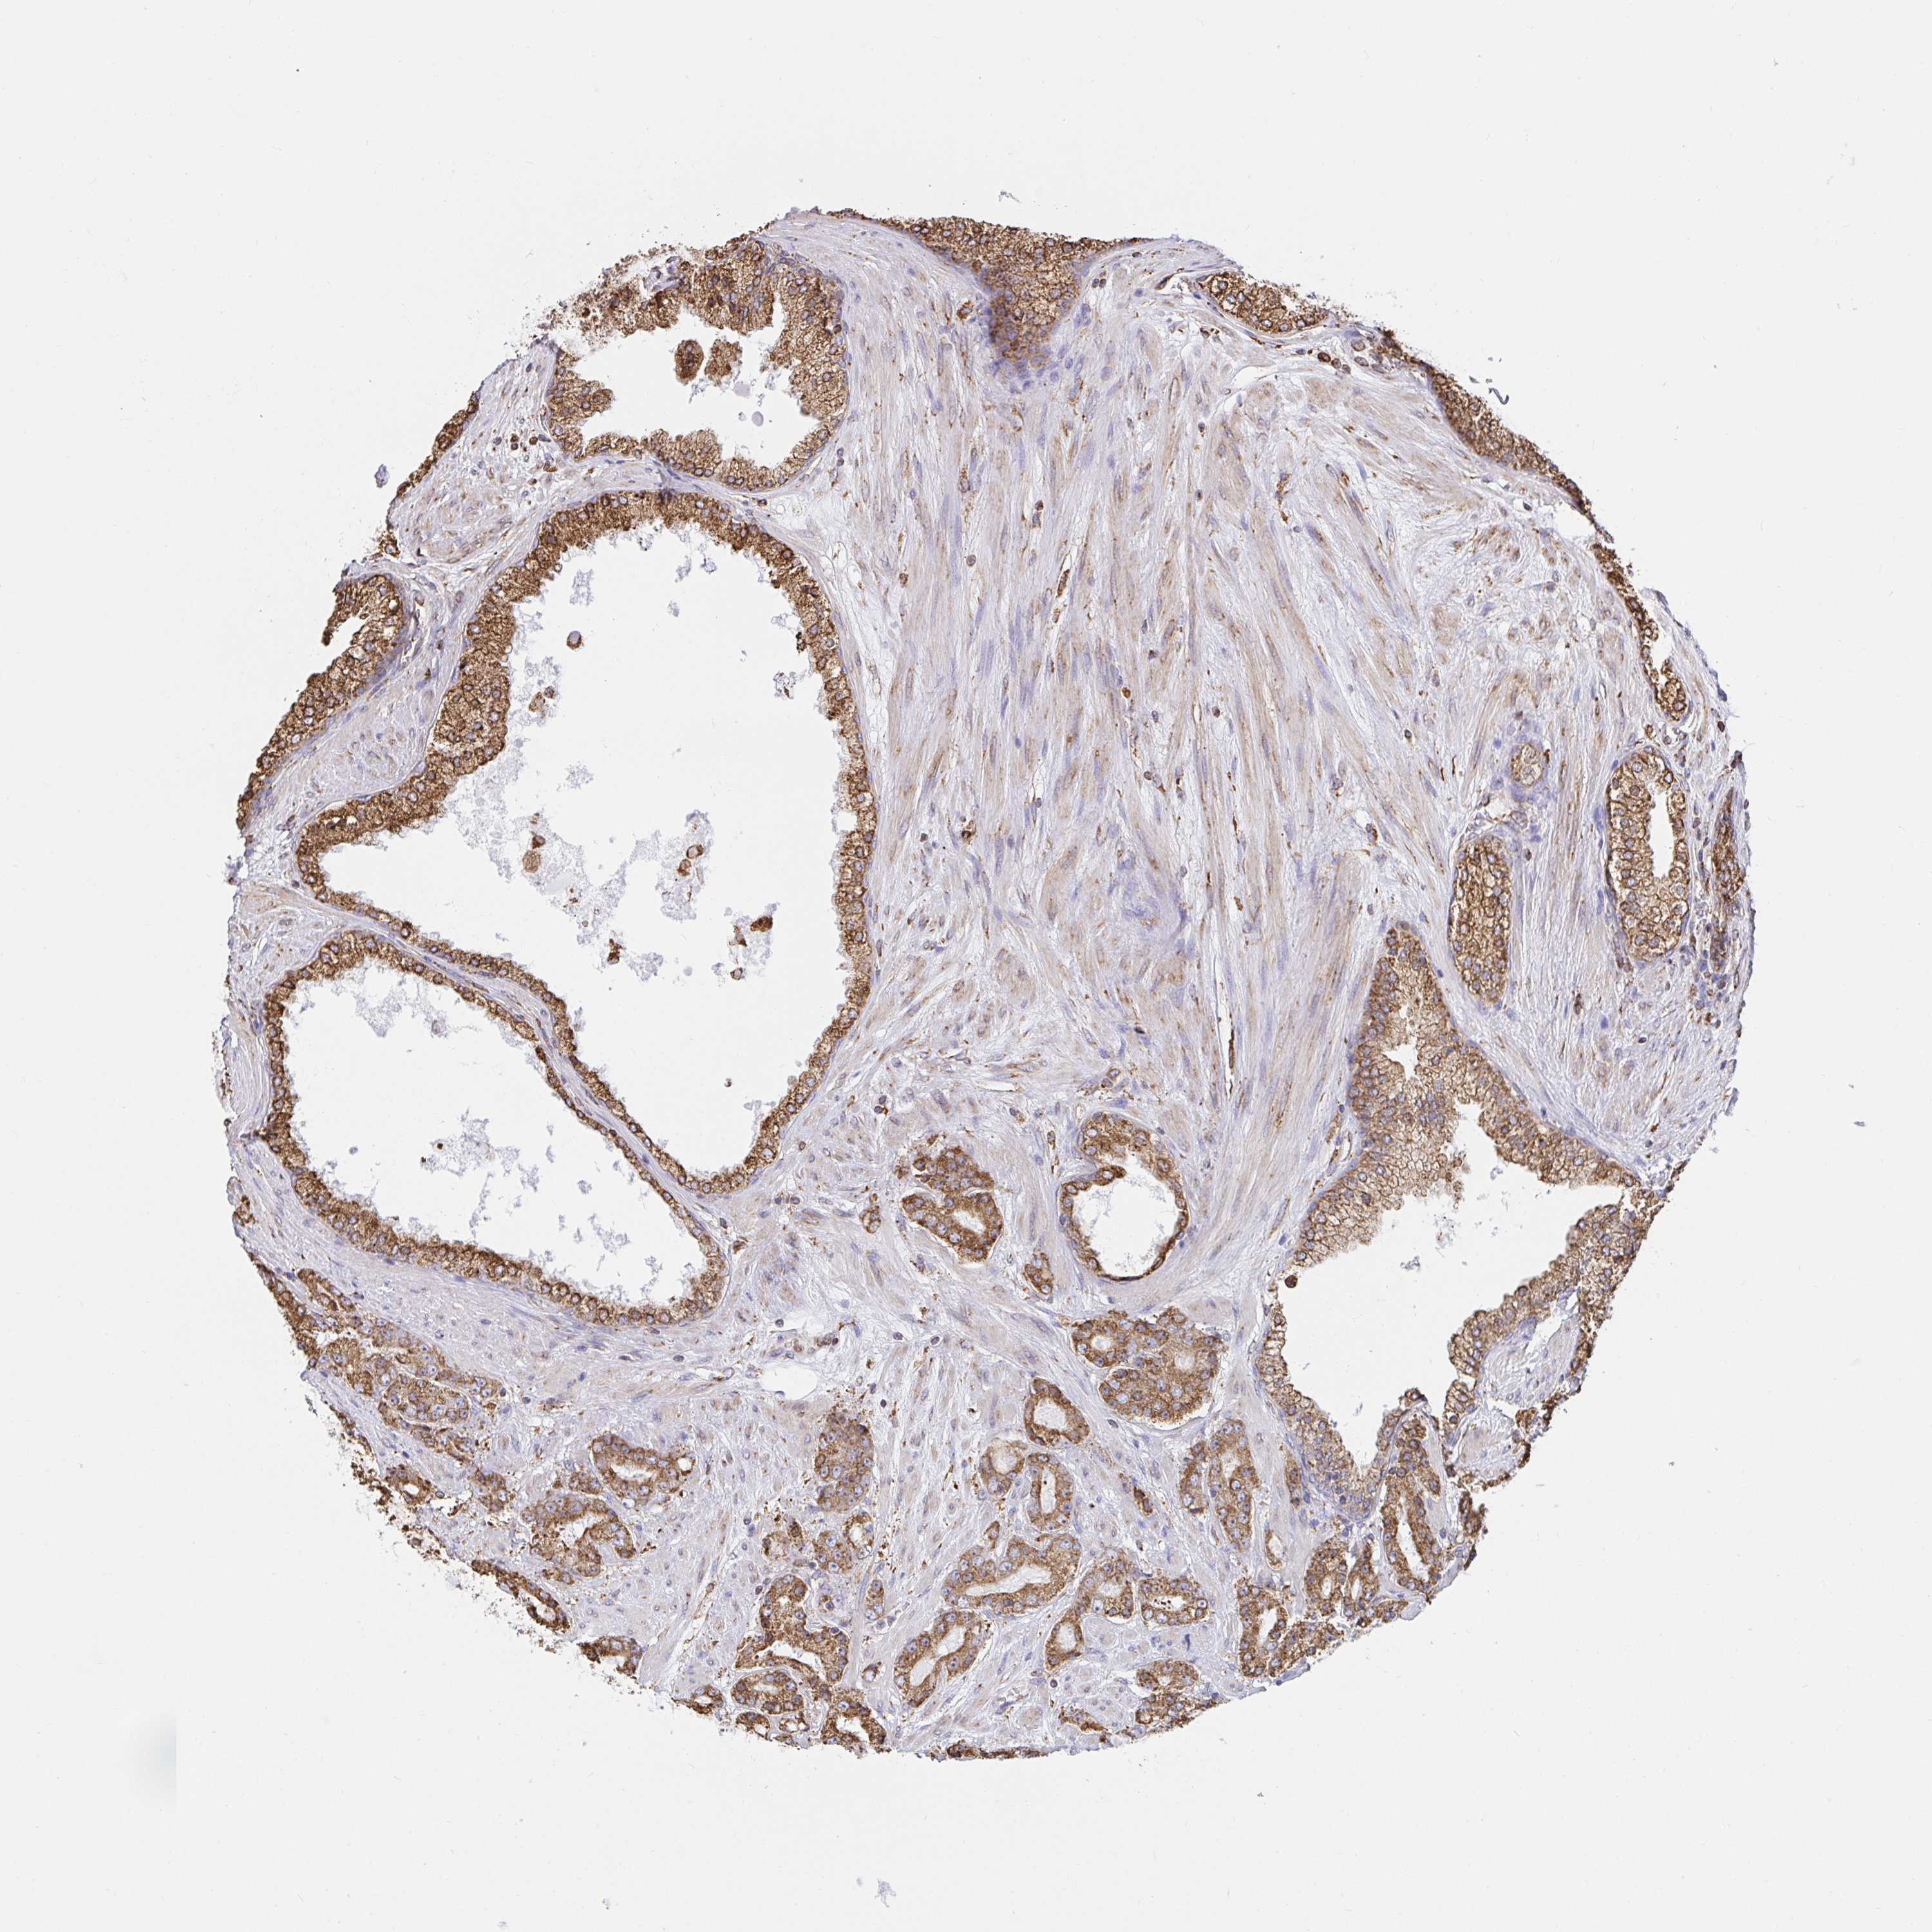

PROSTATE CANCER - Protein expressioni

A mouse-over function shows sample information and annotation data. Click on an image to view it in a full screen mode. Samples can be filtered based on level of antibody staining by selecting one or several of the following categories: high, medium, low and not detected. The assay and annotation is described here.

Note that samples used for immunohistochemistry by the Human Protein Atlas do not correspond to samples in the TCGA dataset.

Antibody stainingi

Antibody staining in the annotated cell types in the current human tissue is reported as not detected, low, medium, or high, based on conventional immunohistochemistry profiling in selected tissues. This score is based on the combination of the staining intensity and fraction of stained cells.

Each image is clickable and will lead to virtual microscopy that enables deeper exploration of all samples and also displays staining intensity scores, fraction scores and subcellular localization as well as patient and tissue information for each sample.

Antibody HPA048761

Antibody HPA058627

Antibody CAB020709

Staining

High

Medium

Low

Not detected

Intensity

Strong

Moderate

Weak

Negative

Quantity

>75%

75%-25%

<25%

None

Location

Nuclear

Cytoplasmic/membranous

Cytoplasmic/membranous,nuclear

Adenocarcinoma, High grade

Adenocarcinoma, NOS

Adenocarcinoma, Low grade